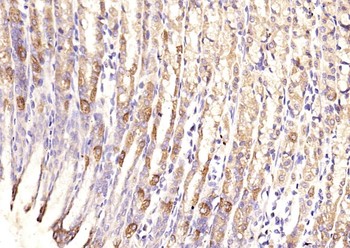

Fixative-fixed, paraffin embedded (human gastric), Antigen retrieval by boiling in sodium citrate buffer (pH6.0) for 15 min, Block endogenous peroxidase by 3% hydrogen peroxide for 20 minutes, Blocking buffer (normal goat serum) at 37°C for 30 min, Antibody incubation with (TSSC3) Polyclonal Antibody, Unconjugated (orb100815) at 1:200 overnight at 4°C, followed by operating according to SP Kit (Rabbit) instructionsand DAB staining.

Fixative-fixed, paraffin embedded (rat stomach), Antigen retrieval by boiling in sodium citrate buffer (pH6.0) for 15 min, Block endogenous peroxidase by 3% hydrogen peroxide for 20 minutes, Blocking buffer (normal goat serum) at 37°C for 30 min, Antibody incubation with (TSSC3) Polyclonal Antibody, Unconjugated (orb100815) at 1:200 overnight at 4°C, followed by operating according to SP Kit (Rabbit) instructionsand DAB staining.